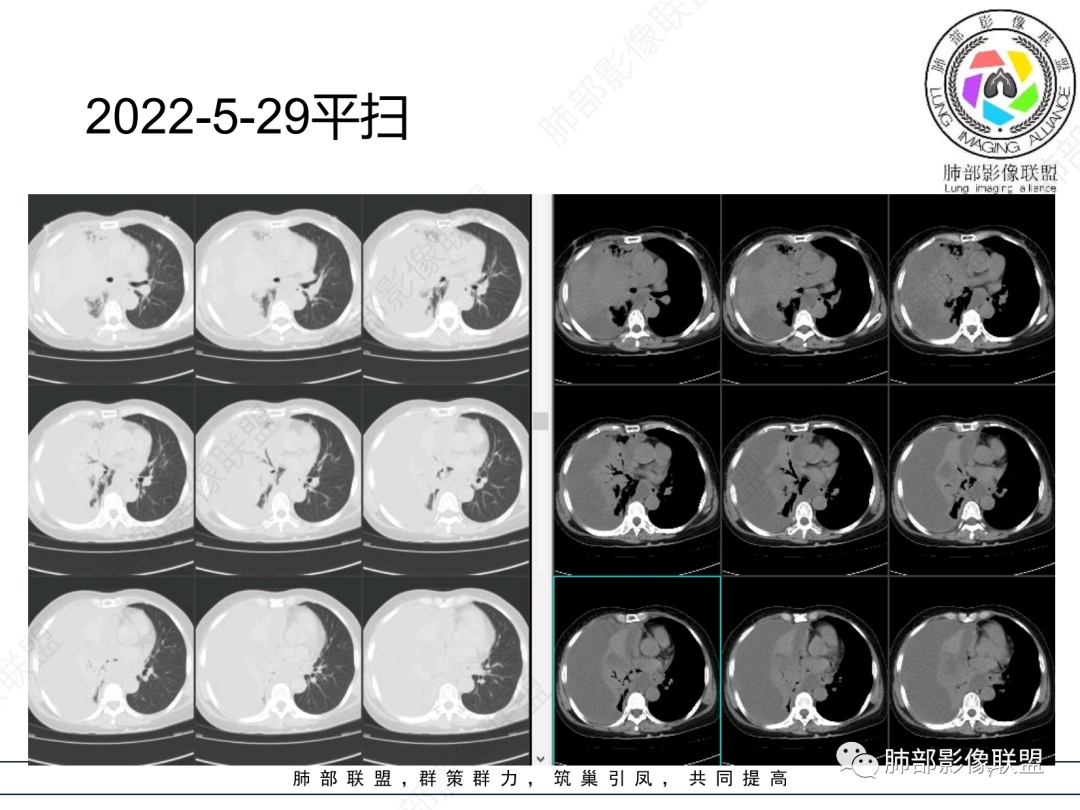

第一次CT:

第二次CT:

中老年女性,急性病史,全身症状,提示全身多部位受累。5,29:右肺大量胸水压迫,导致肺叶不张夹杂其中,无法观察病灶实质;左肺病灶沿支气管血管束走向,无叶段性分布,提示间质为主病变。

10天后:胸水减少,右肺病变较前增大,内部未见坏死,含气支气管通畅。

第一次的

胸腔积液

整体病灶边缘膨隆,周围网格+GGO

肺门区支气管受压、狭窄

从现在的图像看:胸水压迫、推移。

复查左肺病灶没好转

也不符合急性炎症特点

还有一次CT: